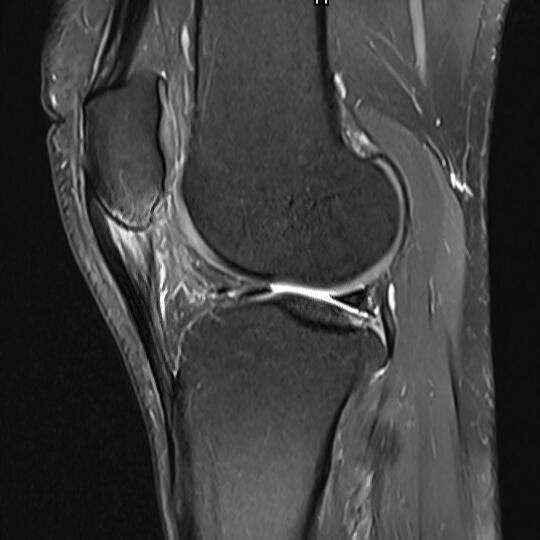

Patellar tendinopathy (MRI scan)